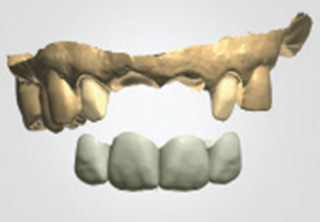

흔히 "네비게이션 임플란트"라고 말하는 컴퓨터 분석을 이용한 임플란트란?

컴퓨터 분석을 이용한 임플란트는 3차원 영상 분석을 통하여 적절한

임플란트의 식립 위치와 방향 등을 결정하여 치료계획을 수립하고,

이를 토대로 개별 맞춤 수술유도장치를 제작하여 시술하는 방법입니다.

3D 모의시술로 식립

시술 전 3D영상장치 등을 통한 진단계획과

모의 수술을 통해 환자의 골조직과 신경관의

위치 등을 파악하여 명확한 치료 계획을

수립하고 개별 맞춤 수술유도장치를

사용하므로 신경 손상 및 부정확한 임플란트

시술의 위험이 적습니다.